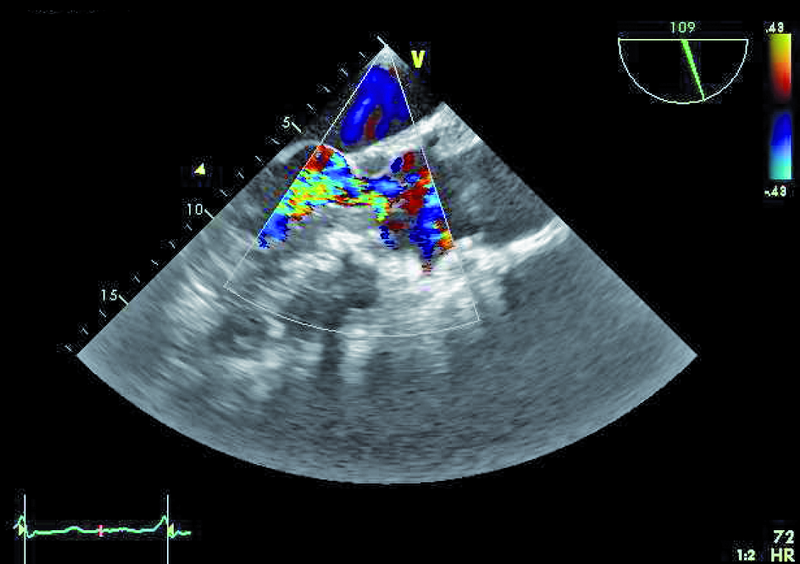

Mężczyzna, lat 25. Jakie patologie można rozpoznać na rycinach?

4. Mała niedomykalność aortalna (ryc. 3, 4).

5. Zwężenie drogi odpływu lewej komory (LVOTO) (ryc. 4, 5).